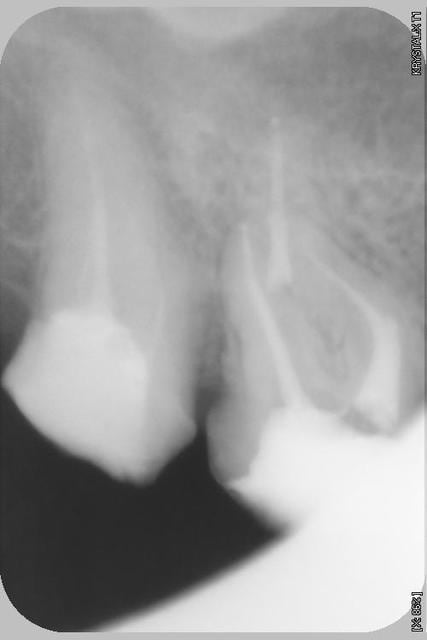

Patiente adressée, douleurs chronique sourde depuis 5 ans au niveau de la 16, ses differents dentistes depuis ne voulaient pas lui demonter la couronne en absence de signes radiologiques.(Ironie du sort je fais parti de ces differents dentistes puisque j'avais moi meme recue cette patiente en urgence en 2007!)

Heu...pour la couronne je ne me souviens plus (mais la douleur etait percistante apres que la couronne ai sauté) par contre ta question m'a remis le nez sur la radio de 2007,( ce n'est pas moi qui ai viré la couronne), et en fait il n'y a pas de tenon ce que l'on voit tres dense c'est l'obturation du MV...je pense, a l'epoque je ne faisais pas grand cas des angulateurs!!! ;)